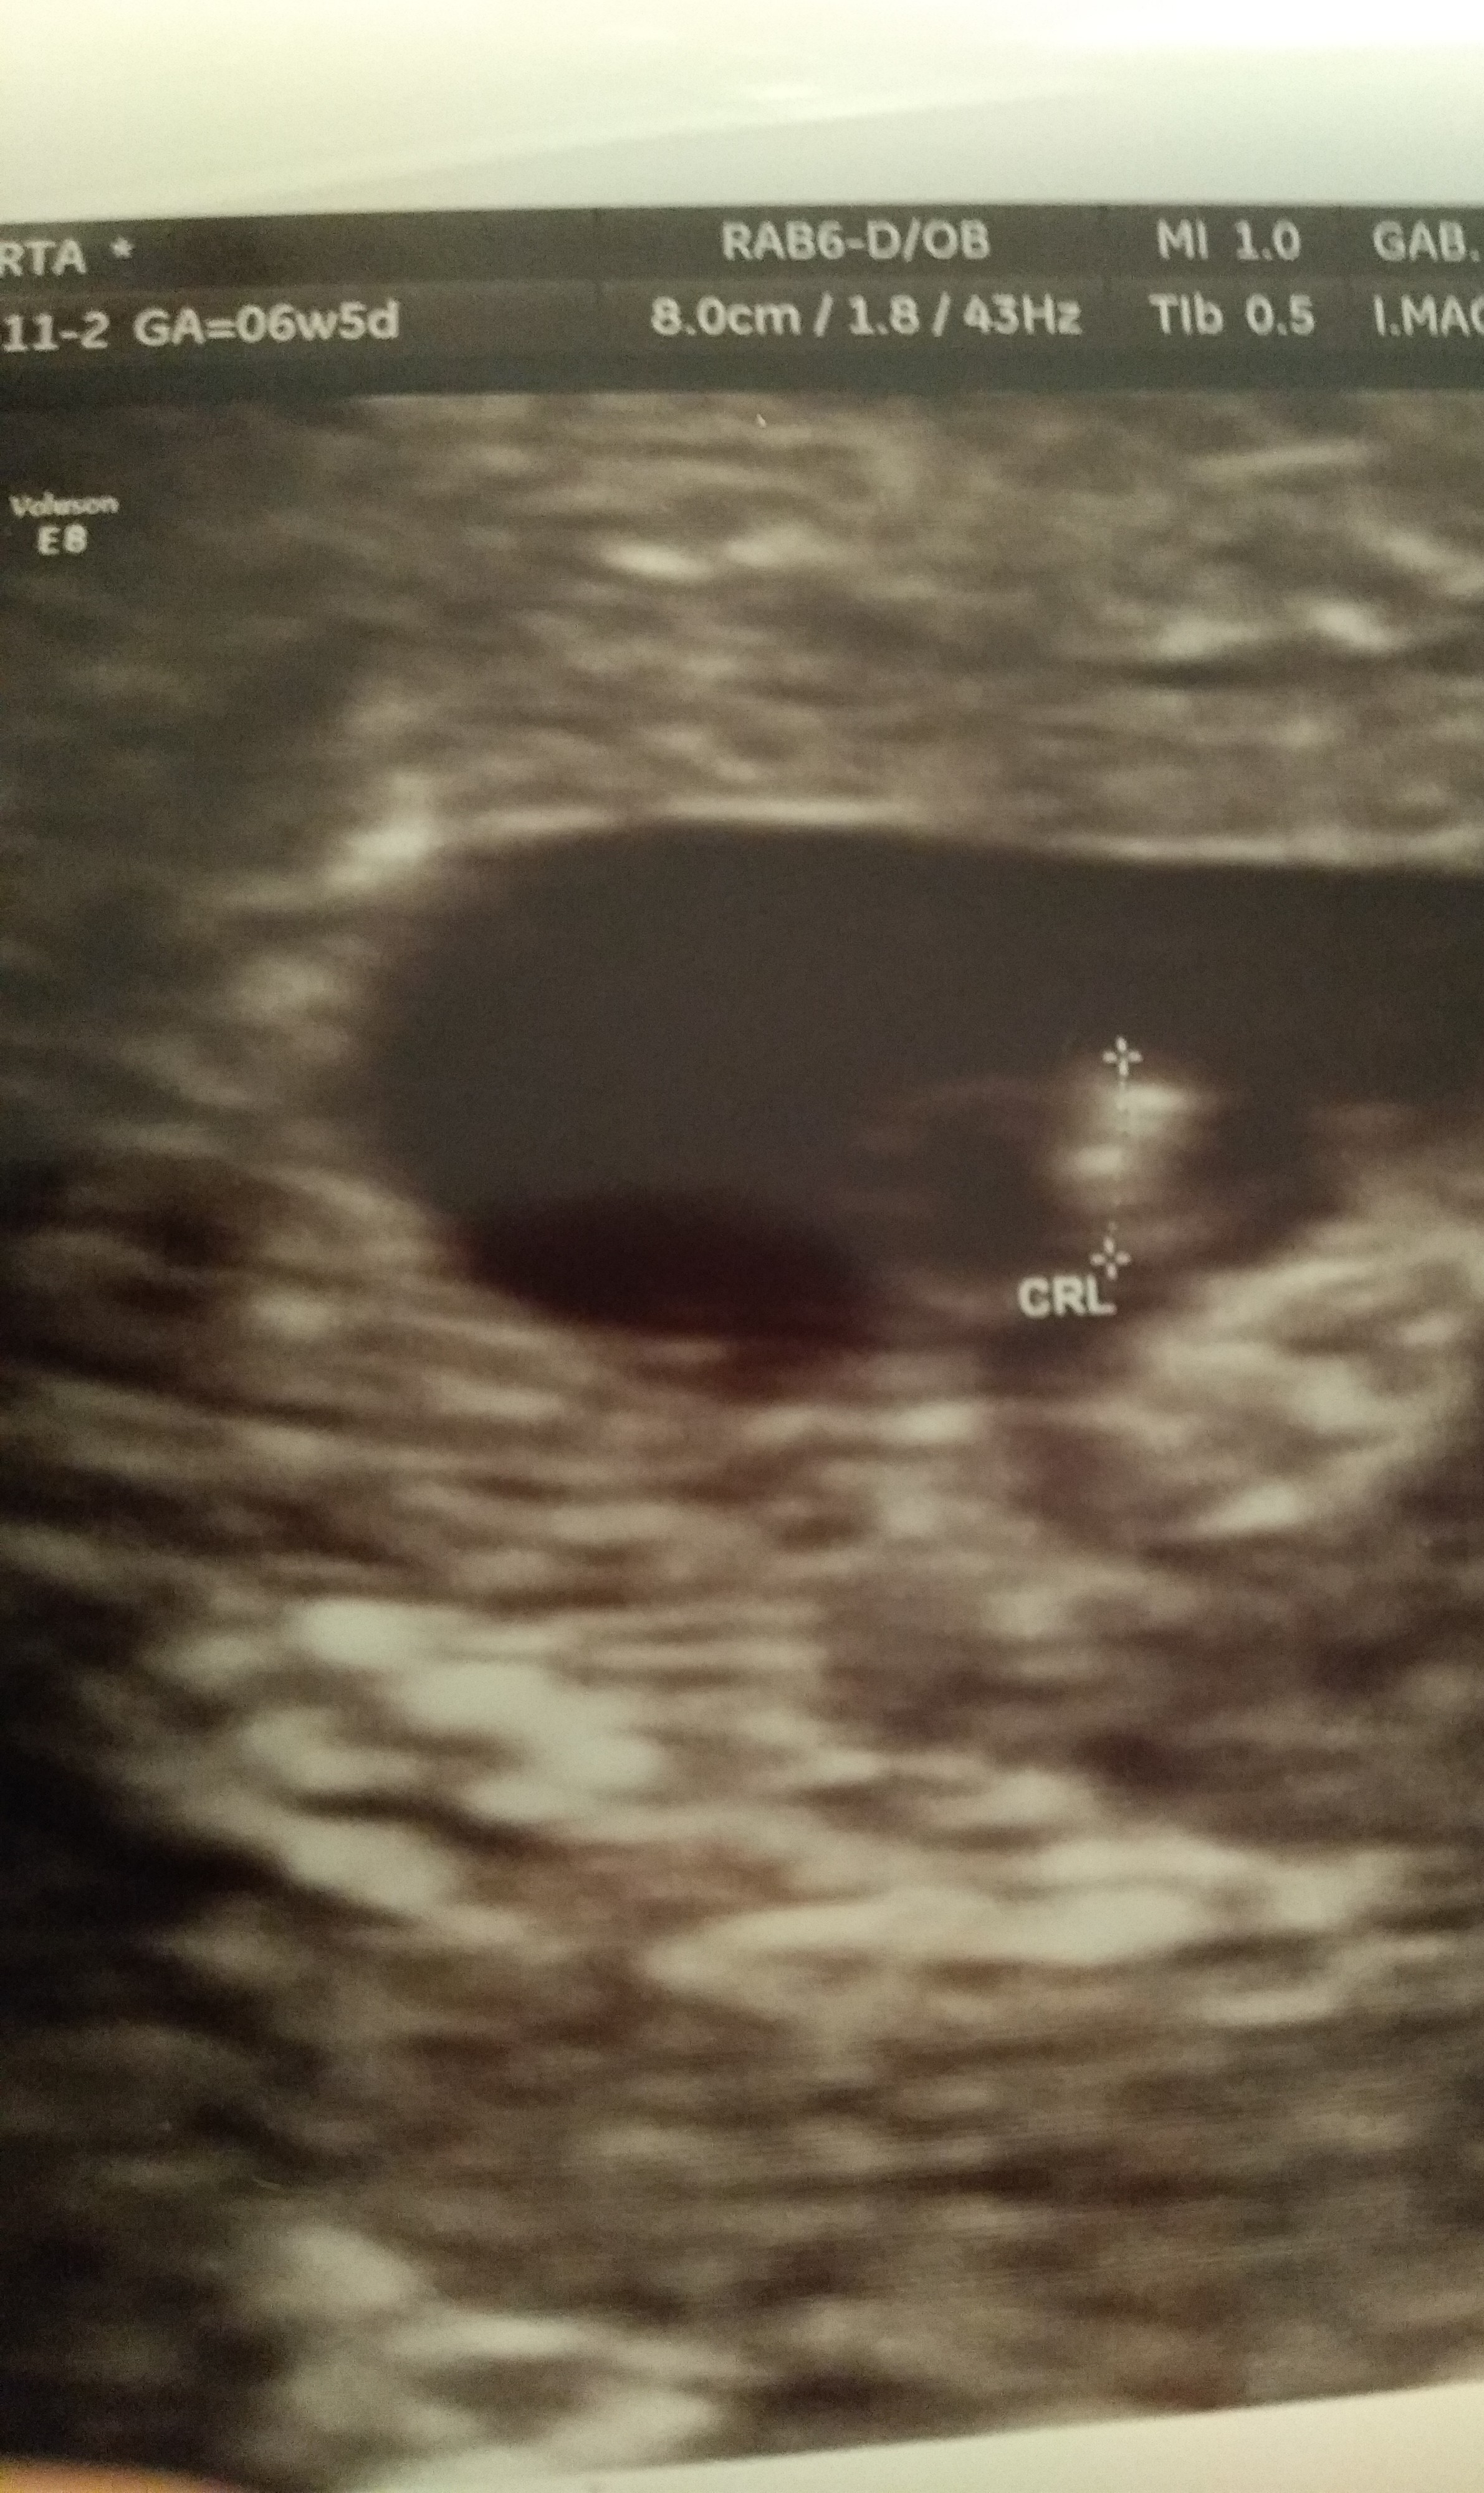

Byłam dziś u lekarza bo zaniepokoiła mnie zielonkawa wydzielina. Okazało się że nic groźnego i powinno obejść się bez leków ale ja szoku doznałam tam na tej kozetce bo okazało się że mamy 2 kropeczki [emoji85][emoji33][emoji854][emoji16]

Dwukosmowkowa, stwierdził że dzieciaczki będą miały oddzielne łożyska. I więcej nie pamiętam.. Następna wizyta 21 września.. Zobacz załącznik 1019385

Dwukosmowkowa dwuowodniowa więc najbardziej korzystna. A czy jednojajowe czy nie to się jeszcze okaże. Moje też mogą być jednojajowe pomimo oddzielnych talerzyków i baseników [emoji4]